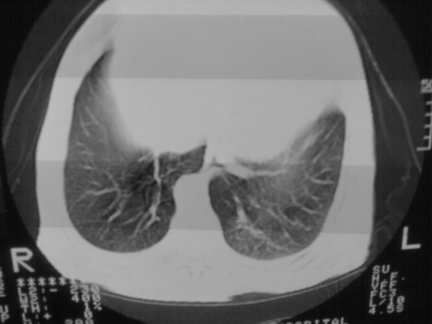

标题: CT13142:女 80 胸闷、气短、1w [打印本页]

标题: CT13142:女 80 胸闷、气短、1w

右肺炎性变,双侧甲状腺肿,胸膜肥厚。

右肺炎性变

双侧胸腔积液

缩窄性心包炎

左室为主的心脏增大。

胸膜肥厚,

气管,支气管软骨钙化。

右肺感染;双侧胸腔少量积液,心影增大,可能与心功不全有关;胸内甲状腺肿。

右肺炎性变,双侧甲状腺肿,胸膜肥厚,心影增大考虑心功能不全.

胸内甲状腺肿;右肺感染;双侧胸腔少量积液。

胸内甲状腺肿;右肺中叶感染;双侧胸腔少量积液;心影增大,考虑有心功能不全。